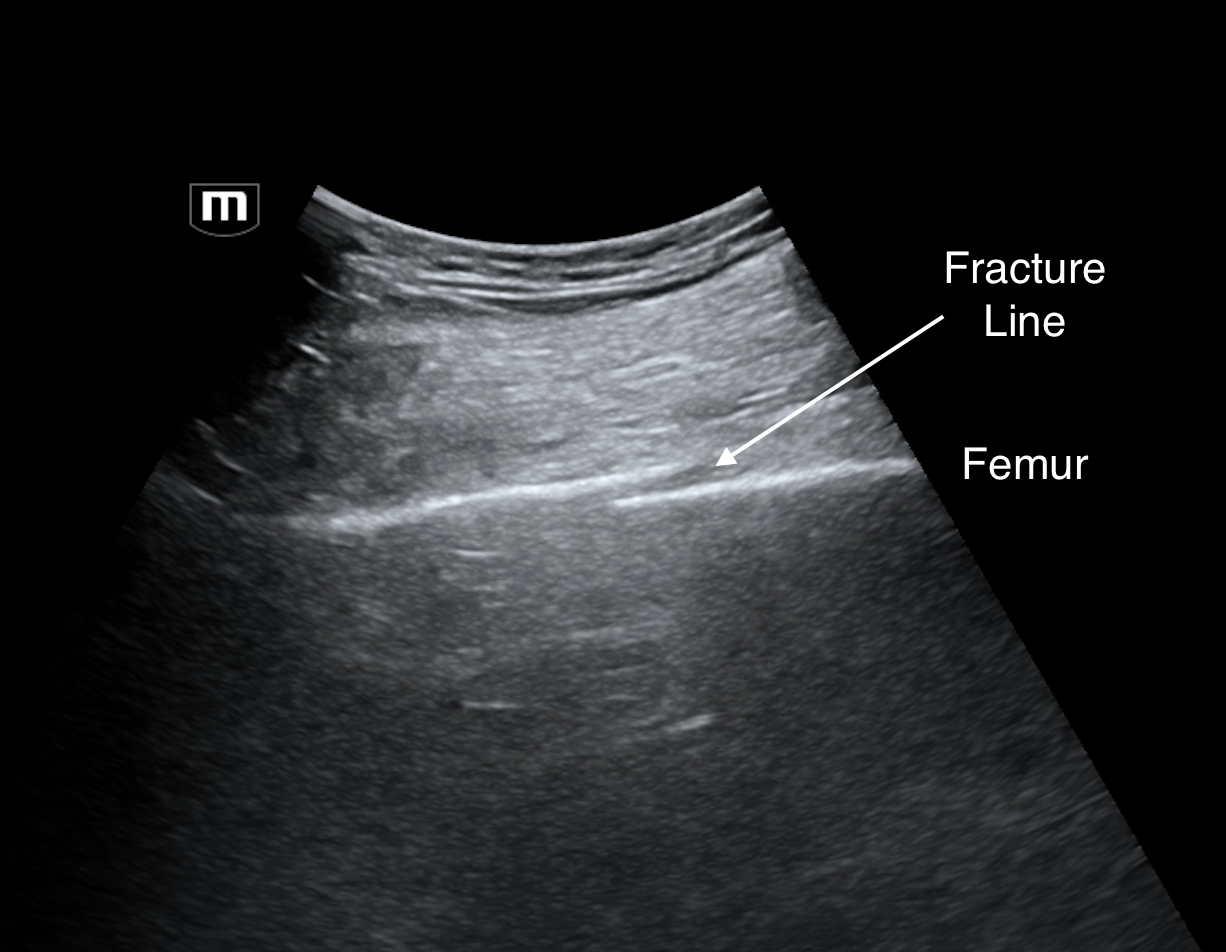

US showed a lovely periprosthetic fracture. In the adult leg, I use the abdominal transducer because it has greater depth penetration and good superficial resolution. But if you wanted better images, you could use a linear transducer.

When looking at a bone, you want to see a bright hyperechoic line with shadowing posteriorly. Fan medially and laterally until the bone line is crisp and thin, then translate the transducer inferiorly or superiorly looking for a break in the line suggesting a fracture.

R femur long (annotated below)